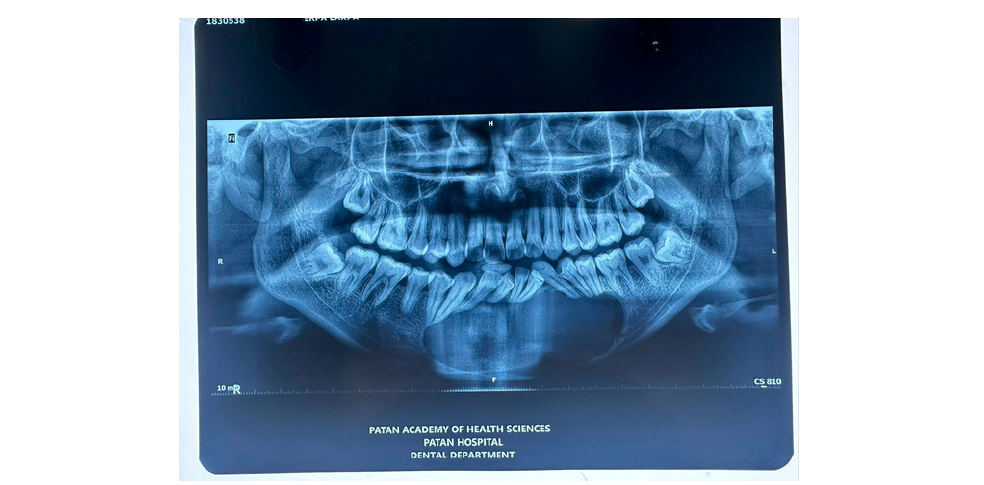

Therefore, CT is considered superior to conventional radiography for differentiating OKCs from other unilocular or multilocular osteolytic lesions and for providing essential information during preoperative assessment (Figure 4). In the mandible, OKCs typically exhibit mesiodistal growth along the length of the bone, resulting in minimal buccal or lingual cortical expansion. However, in some cases, OKCs may produce appreciable expansion and even erosion of the cortical plates (Figure 4).

Figure 4:

Mandibular OKC

Panoramic (a) and cross-sectional (b) Cone Beam Computed Tomography (CBCT) images show an osteolytic odontogenic lesion in the posterior left mandible and ramus, demonstrating growth primarily along the length of the bone (double-headed arrow) with only minimal expansion of the buccal and lingual cortical plates (curved arrows) (Figure 5a). Mesial displacement of the impacted third molar and inferior displacement of the mandibular canal (arrowheads and dots) are evident. A small, incomplete internal septum (small black arrows), reflecting endosteal scalloping of the cortical plate, is also visible. The wavy arrow indicates the mandibular foramen. Panoramic CBCT imaging with a 20-mm slice thickness (a) shows a mandibular OKC containing a septum (opposing arrows) that appears to divide the lesion into two major loculations. Displacement of adjacent teeth is evident (Figure 5b). However, panoramic (b) and axial (c) CBCT images reconstructed at 0.5-mm and 0.2-mm slice thicknesses, respectively, demonstrate that the septum is actually incomplete (arrows). Perforation of the buccal cortex in the anterior portion of the lesion is also visible (curved arrows).